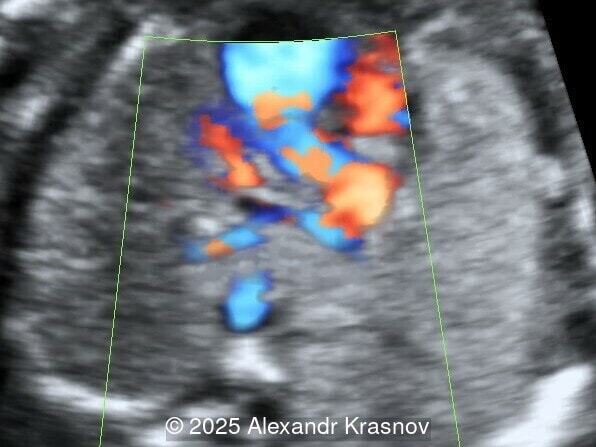

Our ultrasound showed biometry data corresponding to 21 weeks of gestation. During echocardiography, an abnormal drainage of the pulmonary veins was detected in which the pulmonary veins drain into a venous collector linked to the superior vena cava. The four-chamber view and the three-vessel view were altered and raised suspicion of a pathology. The grayscale and color Doppler images of the four-chamber view indicate a smooth posterior wall of the left atrium, increased distance between the left atrium and the descending aorta and the absence of pulmonary veins entering the left atrium (Image 1, 2; Video 1, 2). In the three-vessel view, the diameter of the superior vena cava appears larger than that of the aorta (Image 3, Video 3). In the images of the venae cava, a significant difference is seen between the diameters of the inferior and superior vena cava with significant enlargement of the superior vena cava (Image 4, Video 4). Additionally, there is a pulmonary venous confluent chamber (“twig sign”) behind the left atrium (Image and Video 5). A vertical ascending vein connects the confluent chamber with the superior vena cava where it drains blood from the pulmonary veins (Images 6, 7; Video 6).

Direct markers are based on anatomical features in TAPVR, and their presence usually confirms the diagnosis. Some appear in all types of TAPVR, and others are specific to particular types. A lack of connection between the pulmonary veins and the left atrium or the presence of a confluent chamber can be found in all types of TAPVR. Whereas the presence of an ascending or descending vertical vein is found in supracardiac or infracardiac types. Normal entry of a left and right pulmonary vein at the posterior wall of the left atrium (horn‑like insertion) is absent, which leads to a completely smooth posterior wall in the four-chamber view [6,7]. The “twig sign” represents the entry of the pulmonary veins into a confluent chamber behind the left atrium [7], and is visible in the four‑chamber view except in the cardiac type. In the cardiac type, the confluent vein is located more inferiorly, below the plane of the four‑chamber view and does not form a twig sign, making it more difficult to detect [5]. In supracardiac TAPVR, an ascending vertical vein can be observed in the 3-vessel tracheal view as an additional vessel, usually located at the left of the main pulmonary artery. In infracardiac TAPVR, the descending vertical vein can be seen as an additional vein in the axial abdominal plane [8].

In many cases, direct signs are not visualized, thus identification of indirect signs allow us to suspect this pathology, not diagnose it. They are based on morphological findings such as increased post‑left atrium space, or on hemodynamic changes such as ventricular disproportion, dilated superior vena cava or coronary sinus, and abnormal Doppler waveforms. The presence of a pulmonary venous confluence leads to an increased distance between the left atrium (LA) and the descending aorta (DAo) [9]. While visualization of the confluent chamber may be difficult, objectively measuring the increase in the space behind the left atrium in an axial section may be easier to verify. Various indices have been proposed for this purpose, the most widely used being the “post‑LA space index” described by Kawazu et al [10]. It is calculated as the ratio of the LA‑DAo distance to the diameter of the DAo, proposing a value ≥1.27 as a potential marker of TAPVR. In clinical practice, a cut-off of 1.0 may be more useful to increase detection rates, although this would be at the expense of more false positives. An alternative marker with a similar diagnostic performance and independent of the gestational age is the “left atrial posterior space to diagonal ratio,” which is calculated by dividing the LA‑DAo distance by the left atrial diameter, with an optimal cut-off ≥0.35 [11]. Asymmetric ventricular chamber dimensions with right heart dominance result from extra‑abnormal flow from the pulmonary veins to the right heart, providing a diagnostic clue for TAPVR [9], but this finding is late and not very specific. In supracardiac TAPVR, anomalous pulmonary venous drainage increases blood flow to the collector, which travels to the right atrium through the dilated innominate vein and superior vena cava, visible in the three-vessel trachea and bicaval views [7,12]. In the subcostal view of pediatric echocardiography, the cardiac type is characterized by the “whale’s tail sign,” where left and right pulmonary veins drain into the dilated coronary sinus. Although it is a technically difficult plane to obtain in fetal echocardiography, it has been described by Karmegaraj in a 25-week-old fetus [13]. Spectral Doppler waveforms are typically normal or biphasic in cardiac type, whereas in supracardiac and infracardiac types, the waveforms can be biphasic, monophasic, or continuous [6,7]. Color and spectral Doppler assessment allows the identification of the fetuses with pulmonary venous pathway obstruction and, therefore, at risk for acute postnatal deterioration with severe respiratory distress and cyanosis [14].